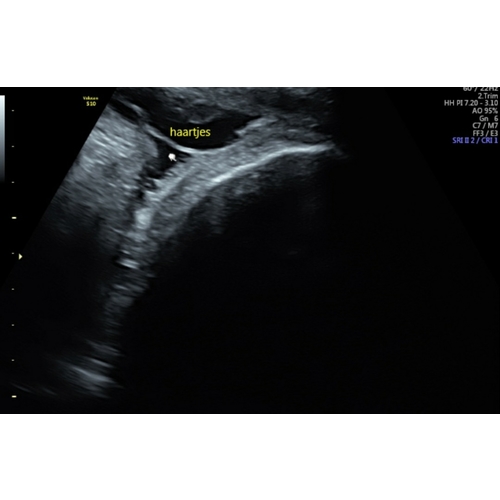

Heeeeel veel maagzuur hier, en ook een vol koppie haar(helaas weer uitgevallen..😞) Was ook op de echo al te zien, dus misschien kun je je verloskundige vragen er naar te kijken 😁